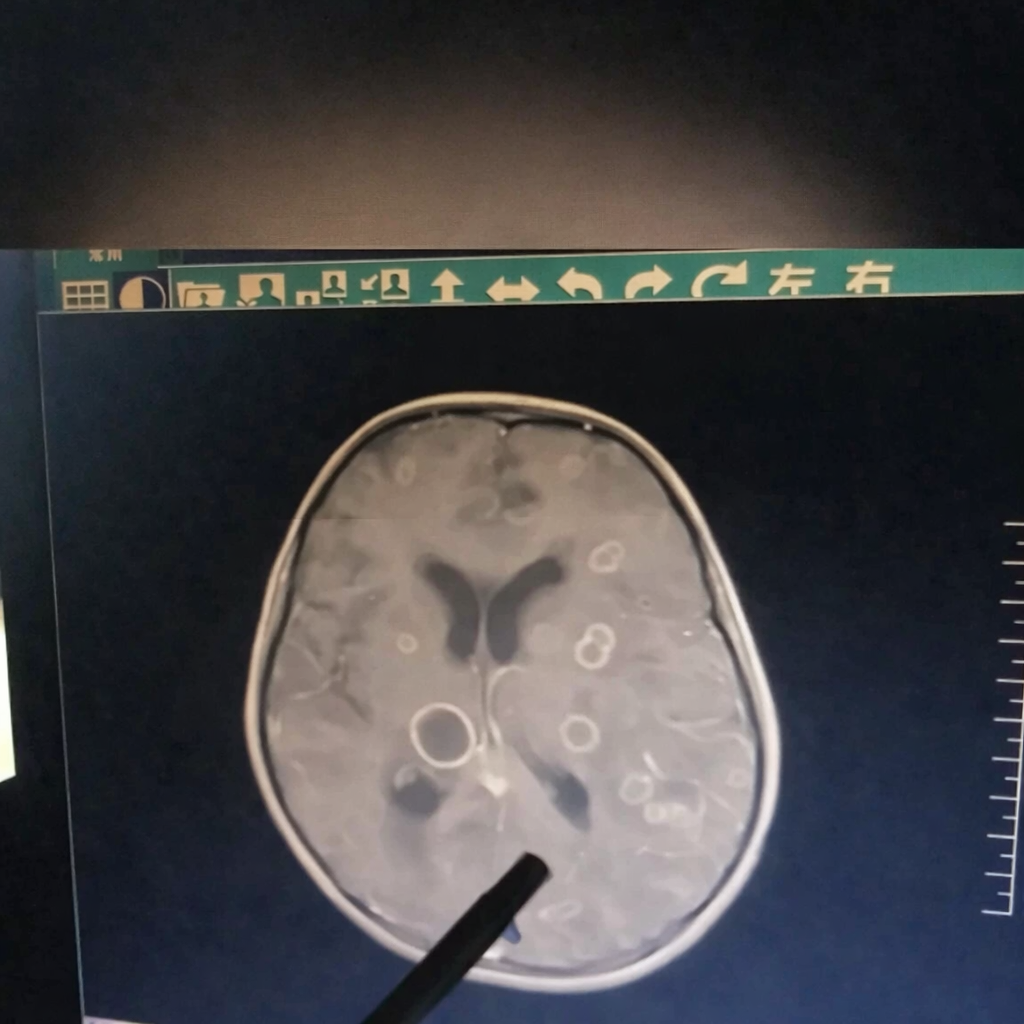

Kết quả kiểm tra khiến các bác sĩ không khỏi bàng hoàng: trong não của đứa trẻ xuất hiện hơn chục ổ tổn thương lớn nhỏ, giống như bị “gặm nhấm” từng mảng.

Mới đây, một bé gái 6 tuổi ở Trung Quốc bị sốt liên tục suốt 17 ngày, dần rơi vào tình trạng lơ mơ, rối loạn ý thức và được chuyển gấp tới Bệnh viện trực thuộc Đại học Trịnh Châu (Trung Quốc). Kết quả kiểm tra khiến các bác sĩ không khỏi bàng hoàng: trong não của đứa trẻ xuất hiện hơn chục ổ tổn thương lớn nhỏ, giống như bị “gặm nhấm” từng mảng.

Bác sĩ cho biết, nếu đến muộn thêm vài ngày, tổn thương có thể lan rộng đến mức đe dọa trực tiếp tính mạng.